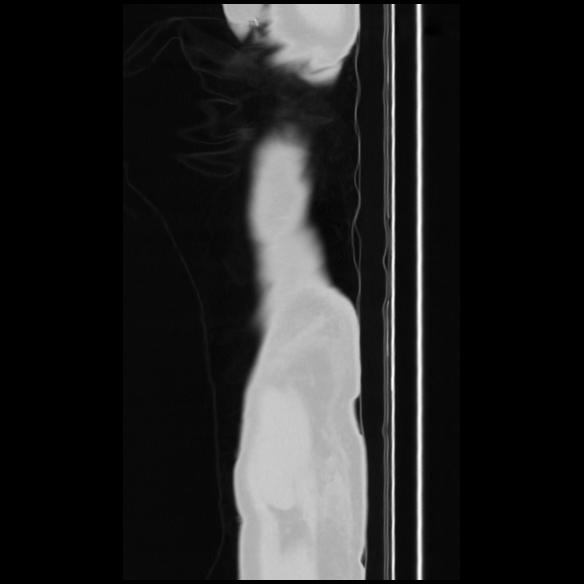

7 CUERPO,CE,Sagittal,3.000,CUERPO,Sagittal,